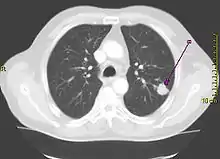

- CT-scanning

CT-scanningen viser en tredimensionel afbildning af brystkassen og den øvre del af mave/bughule. Den viser langt bedre end en almindelig røntgenundersøgelse, om der er tale om kræft, hvor den er lokaliseret, om den har bredt sig til lymfeknuderne i brystskillevæggen, eller om den vokser ind i brystvæggen, ribben eller hvirvelsøjle. Scanningen kan også vise, om der er tegn på spredning (metastaser) til lever, bugspytkirtlen og binyrer.